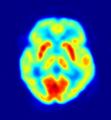

وقد ازداد الاهتمام في الآونة الأخيرة بفرع خاص من الهندسة النووية يعنى بالتطبيقات الإشعاعية في المجالين الطبي والصناعي، حيث يجري التركيز في هذا الفرع على التجهيزات التي تعتمد في عملها على مبادئ الإشعاع، وتجد تطبيقات متزايدة في مجال التشخيص والعلاج الطبي إضافةً إلى التطبيقات الصناعية المختلفة كالاختبارات اللاإتلافية.

الطب النووية والفيزياء الطبية